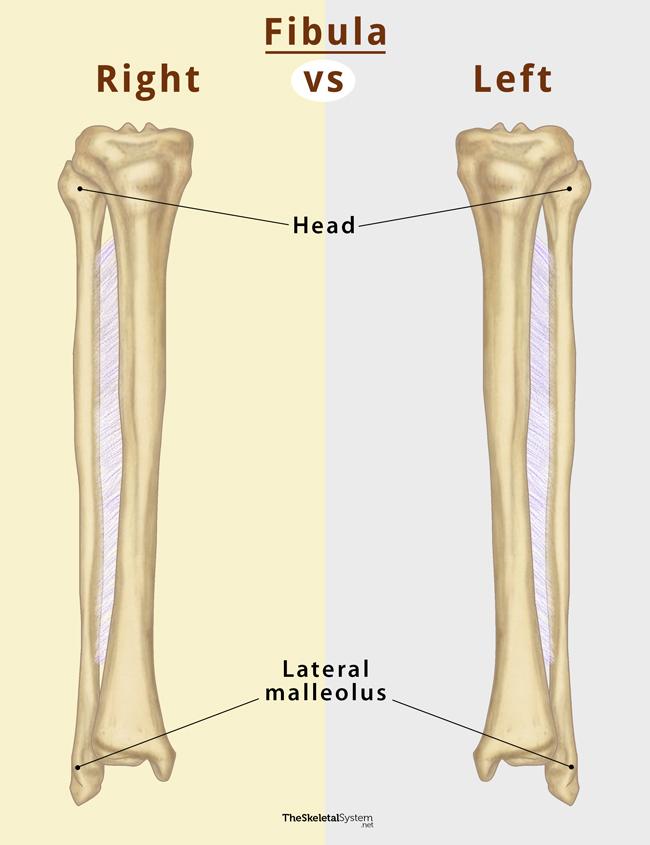

Анатомия фибулы: Подробные фотографии и схемы